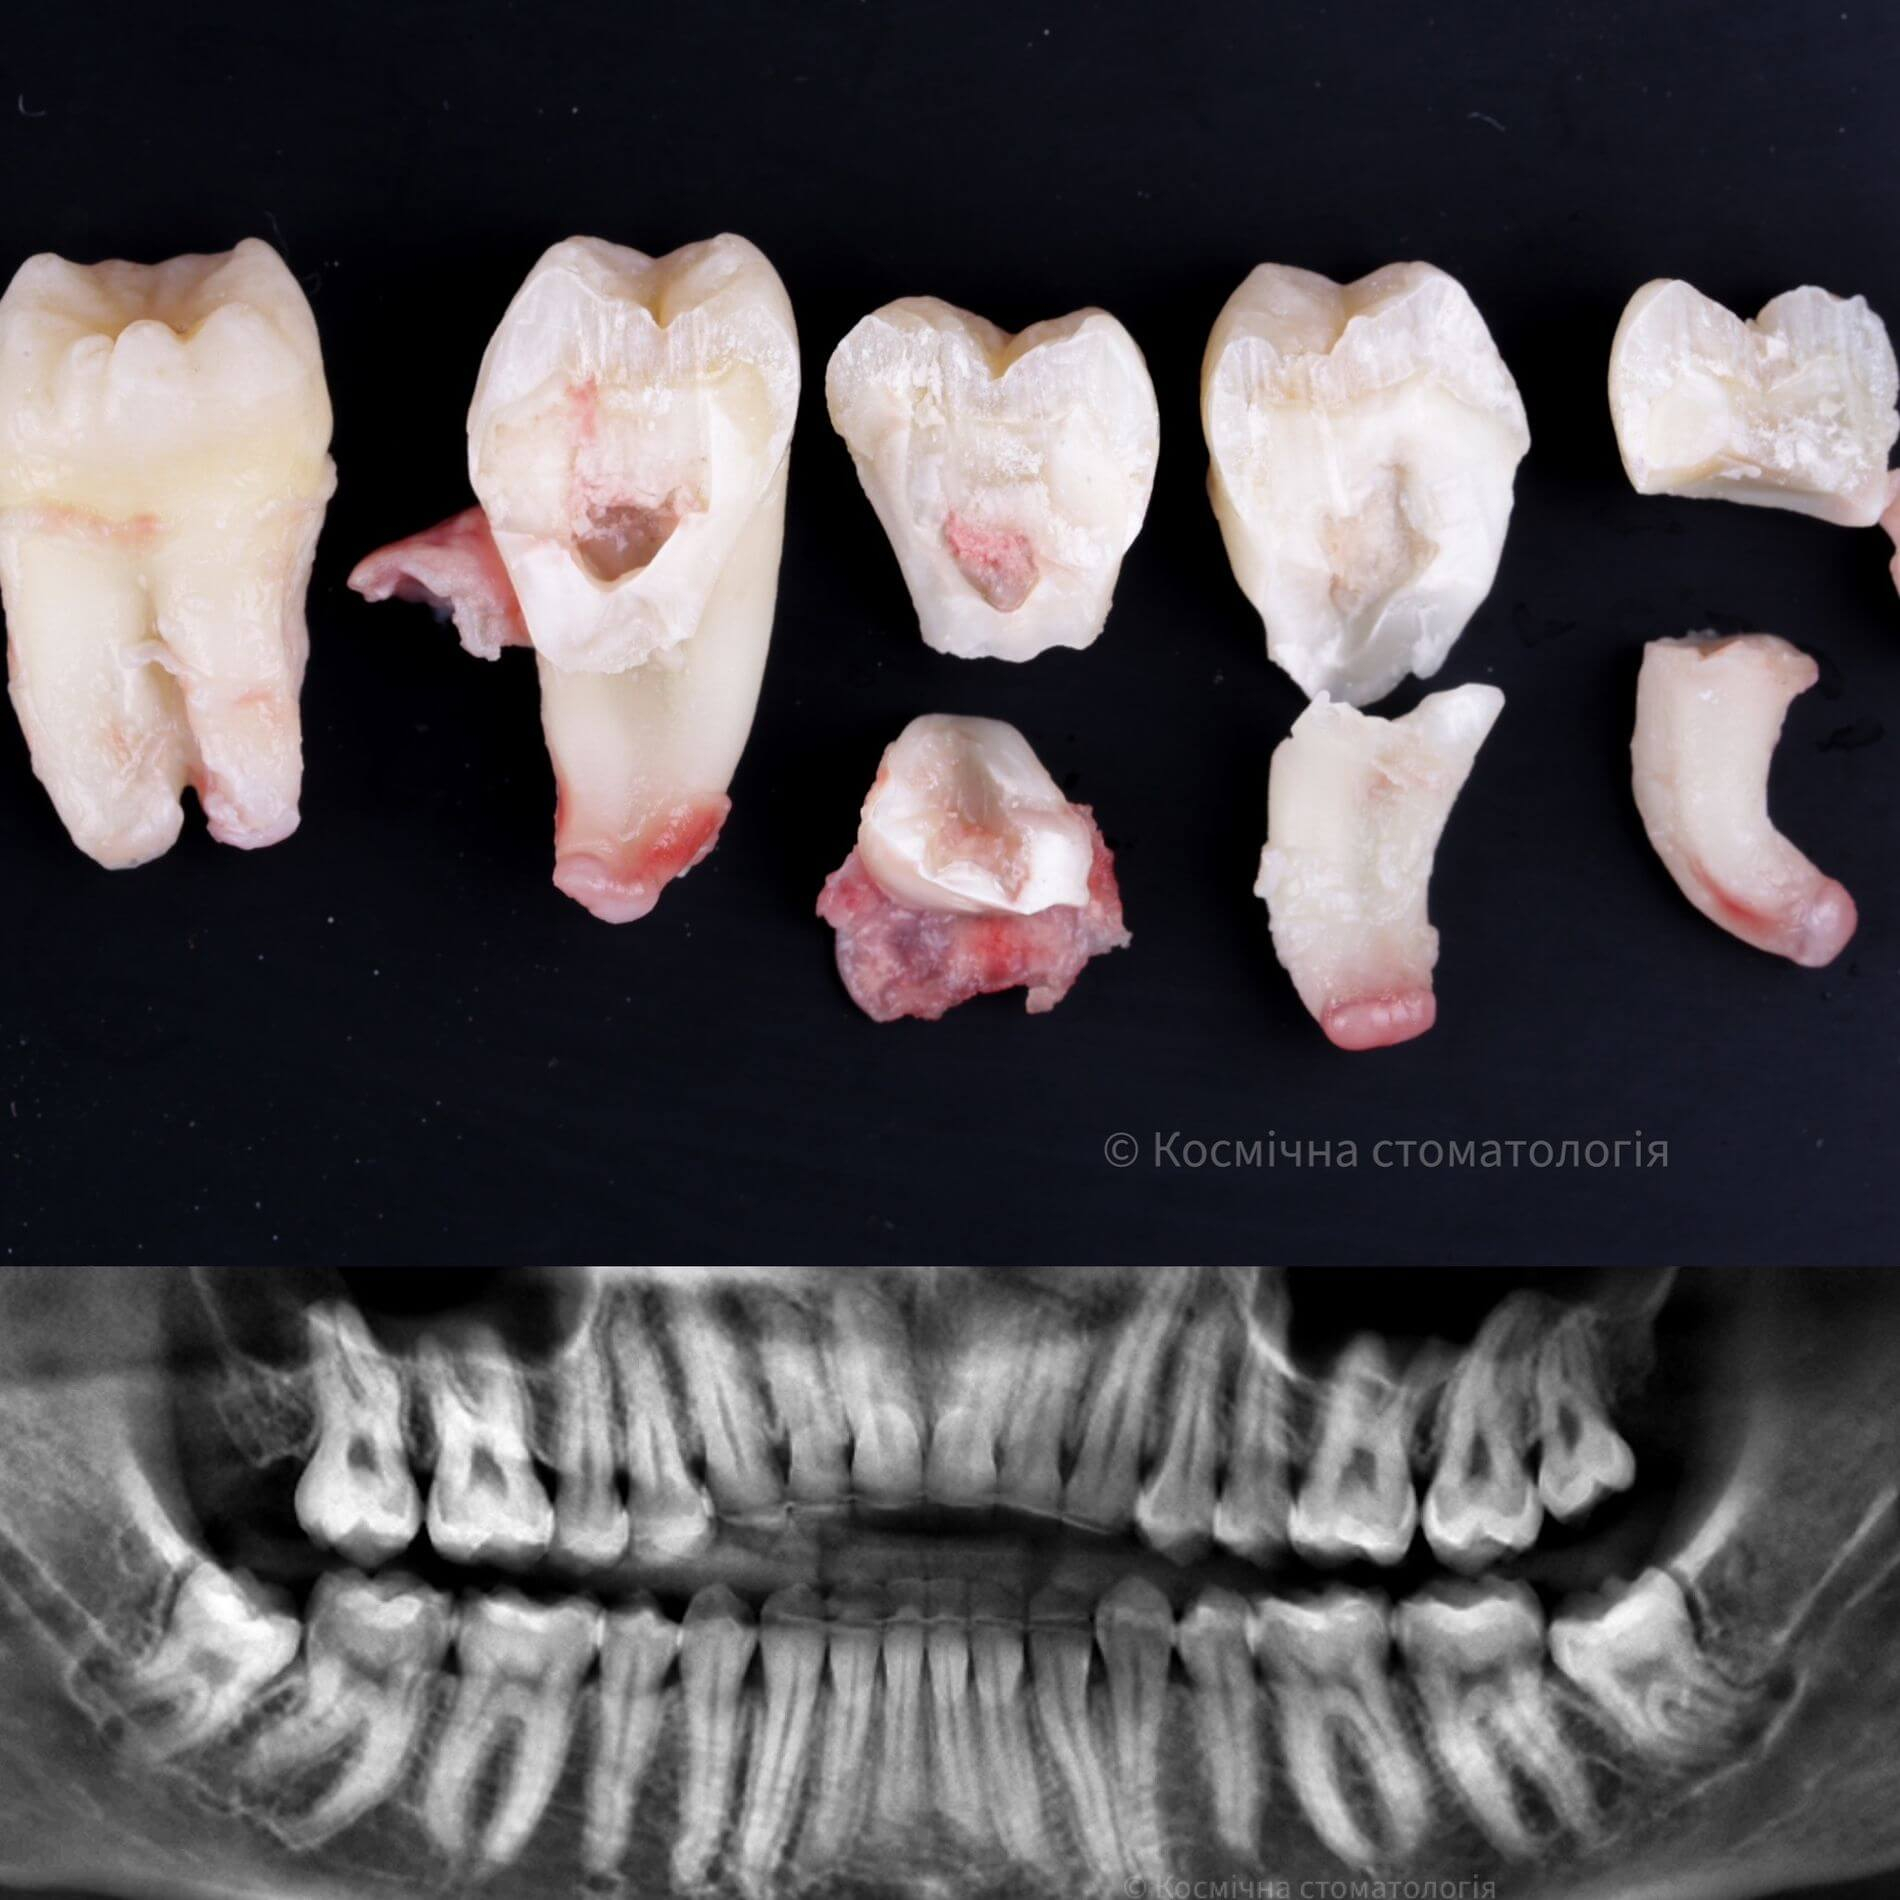

Види видалення зубів мудрості

- Повне видалення зуба - якщо зуб повністю прорізався та має зрощені корені.

- Окреме видалення коронки зуба та його коренів - якщо зуб прорізаний і корені ростуть по окремо.

- Видалення зуба за схемою 1 або 2 із розрізом ясна - якщо зуб прорізаний частково.

- Розріз ясна, звільнення зуба від прилеглої кістки ультразвуком та видалення за схемою 1 або 2 - якщо зуб не прорізався, але турбує.

Галерея